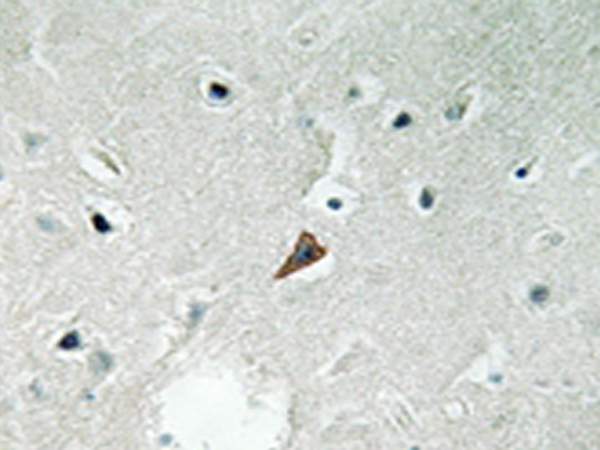

IHC positive control: |

Human brain tissue |

IHC Recommend dilution: |

50-100 |